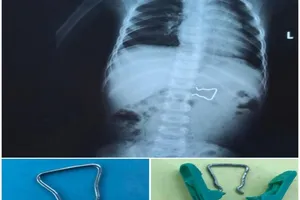

Bé trai 18 tháng suýt thủng ruột vì nuốt móc sắt kẹp áo